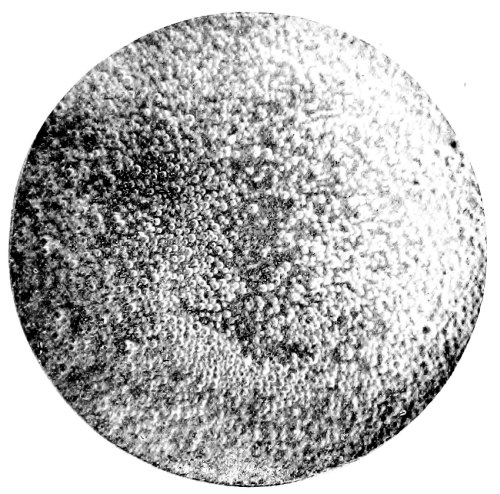

Plate showing Centre of Ossification in the Lower Epiphysi of PAGE

Femur in full time Fœtus To face 64

A plate, showing the centre of ossification in the lower epiphysis of the femur in a full time fœtus, has been introduced at the last moment, and will be found opposite page 64. References to the subject may also be found on pages 33 and 174.